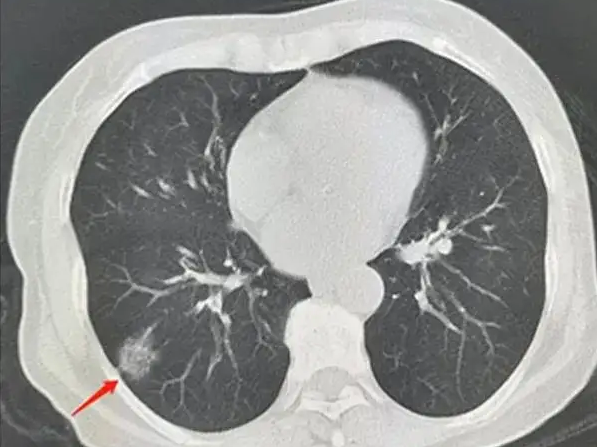

对于肺实性结节,亚厘米的常规胸片不容易发现,除非密度甚高,又在肺外围部位。较大的结节可以在胸片检查中发现,但要进一步判断其性质,胸部CT检查仍是最重要的检查手段。

(1)胸部CT检查:是肺实性结节最主要的检查手段。如果结节较小,细节显示不清,可以加行病灶所在肺叶的靶扫描与重建。它能从各个方向显示病灶形态、边缘、与周围血管支气管的关系等细节。增强CT对于判断肺实性结节的价值远远大于针对磨玻璃结节,可以确实病灶的血供是否丰富,但若病灶为炎性或结核等,有时有强化也并不能判定为恶性。